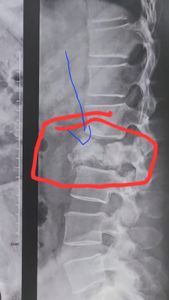

Em 31 de dez de 23, tive um desmaio na de véspera de réveillon onde eu fraturei a coluna. E de lá para cá eu tive mais dois desmaios, uma sequência de crise de pânico devido ao trauma, e um dia tive crise dirigindo, fui socorrido por amigos e familiares, onde eu perdi completamente o sentido cheguei até a pensar que estava perdendo a faculdades mentais. Em janeiro comecei a investigar e descobri que estava com a fratura na coluna através de uma tomografia conforme imagens anexas, que fui ajudado por um anjo da guarda pois eu não tinha um centavo naquele momento. O negócio local tinha parado, eu não estava conseguindo fazer as refeições (marmitas), pois não conseguia ficar em pé.

No começo de maio, fui tomar banho e sofri um acidente no banheiro, onde agravou ainda mais a fratura e de lá para cá, parei de andar no final de Abril para Maio.

Hoje eu já não ando, não sento e só posso ficar deitado.